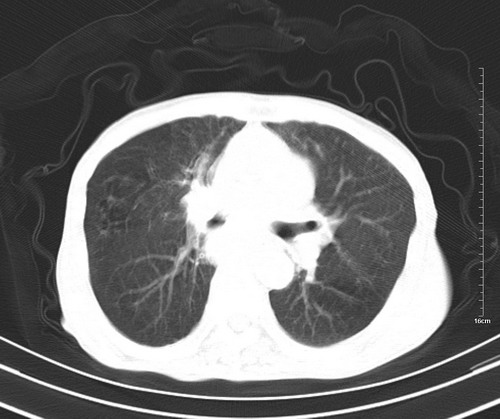

中后纵隔占位,气管、食道受压、变形、移位。恶性可能性大。

考虑:中后纵隔转移瘤可能性大,主动脉硬化。

中后纵隔占位, 考虑:转移瘤不除外.

1 气管旁、隆突下淋巴结明显肿大,肝左叶外侧段低密影,都考虑转移。

纵隔淋巴结肿大,考虑转移而来

肺癌,纵隔淋巴结转移,肝左叶病变考虑为转移病灶。

中后纵隔转移瘤可能性大,主动脉硬化。

中后纵隔转移瘤可能性大

后中纵隔团块影,伴气管、食道受压移位,首先考虑转移瘤,肝s5段低密度灶。建议增强检查,另外其结肠是否有问题请提供,右肺部分肺叶局限含气增多,考虑局限肺气肿。

建议强化检查,考虑纵隔型肺癌,小细胞可能性大。

后中纵隔团块影,伴气管、食道受压移位,首先考虑转移瘤,肝表现同11773。

后中纵隔淋巴结肿大,首先考虑转移瘤。